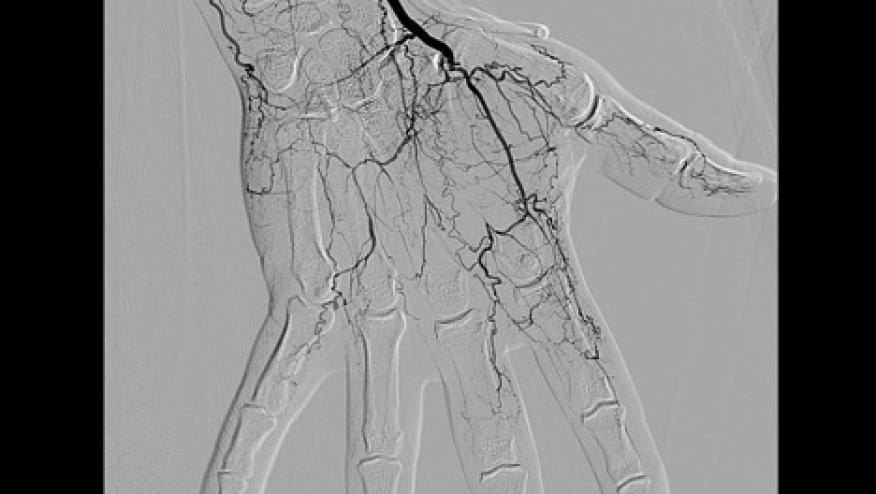

Laboratory evaluation showed normal CBC, chemistries, liver-associated enzymes, urinalysis, sedimentation rate, C-reactive protein, complement levels, ANA, rheumatoid factor, ANCA, cryoglobulins, antiphospholipid antibodies, hepatitis B and C serologies, and SPEP. Urine drug screen was negative except for cannabinoids. He was treated with low dose aspirin, amlodipine, high dose prednisone, and monthly intravenous cyclophosphamide for 4 months. On this therapy, three fingers progressed to gangrene requiring distal phalanx amputation (Figure 1). He was referred and admitted to the University of Colorado hospital. A repeat angiogram of his upper and lower extremities showed multiple distal segmental occlusions and corkscrew collaterals compatible with thromboangiitis obliterans (Figure 2). Further evaluation showed normal lipids, homocysteine, anti-thrombin III activity, and nicotine levels. Anti-prothrombin antibodies and prothrombin gene G20210A mutations were negative.

Figure 2: Right hand angiogram with absent ulnar artery, poor blood flow to digits, and cork-screw collaterals.